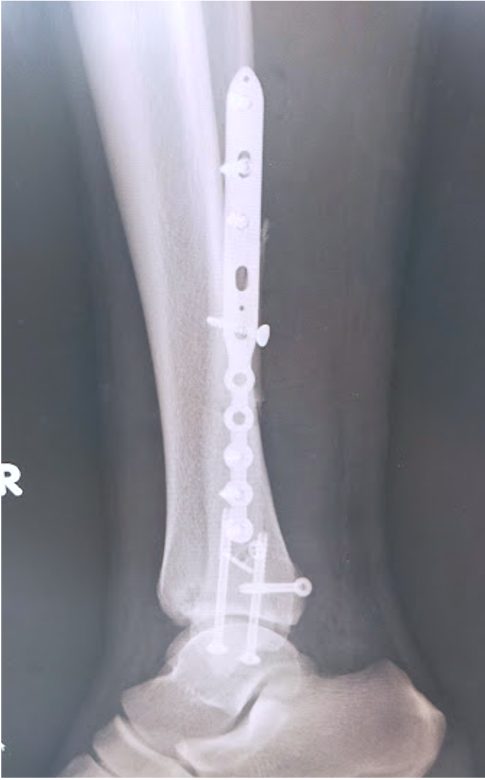

ひざ、股関節を含む、四肢の骨折に対しては、適応があれば手術加療を行い、機能改善および早期の社会復帰を目指しています。

関節を含む骨折は、機能障害を起こしやすく、正確に関節を再建する必要があり、早期リハビリ、機能改善にはとても重要です。

その他、上肢の骨折、足関節や下腿骨などの下肢骨折など、日常的に発生することの多いほとんどの骨折に対する治療に対応しています。

足関節脱臼骨折に対する骨接合術